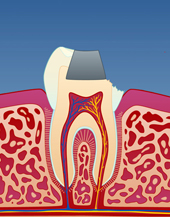

Bildet viser at den gjenstående amalgamfyllingen er fjernet, og at tannen er bygget opp igjen med en plastfylling.

Bruddlinjen førte over tid til at tannen frakturerte.

Den gjenstående amalgamfyllingen ble fjernet, og tannen ble bygget opp igjen med en plastfylling.